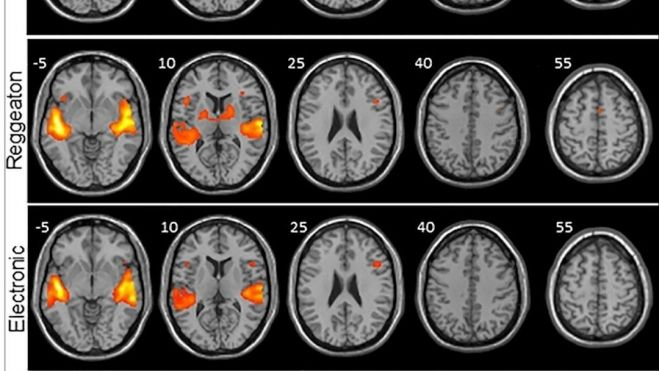

Los investigadores analizaron por un lado anatómicamente el cerebro de cada participante y luego la señal BOLD, que consiste en ver qué áreas del cerebro reclutan oxígeno (que es lo que sucede cuando se activan) y a través de un software se representaron con diferentes colores según se activasen más o menos.La razón por la que se eliminó la letra de los clips musicales de cada estilo es "porque pretendíamos estudiar de la forma más pura posible el procesamiento de la música, y el lenguaje podría (al emplear otras vías neurales) mostrarnos activación cerebral que no es específica de la música".

Y fue el reguetón el que mostró mayor activación en las regiones del cerebro encargadas de procesar los sonidos (áreas auditivas) y de procesar el movimiento (áreas motoras), unas diferencias que resultaron mayores cuando se comparaban con la música clásica.La electrónica también mostró una mayor activación de las regiones motoras, pero significativamente menor en comparación con el reguetón "y lo que más nos llamó la atención fue la activación de una región primitiva del cerebro: los ganglios basales".